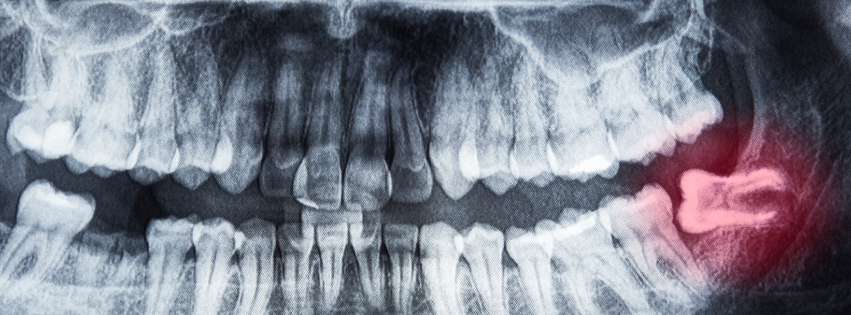

ภาพเอ็กซเรย์แสดงฟันคุดฝังในกระดูก เชียงใหม่ | impacted wisdom tooth in jaw x-ray chiangmai

ควรเริ่มจากการสังเกตอาการผิดปกติในช่องปาก เช่น รู้สึกปวดบริเวณฟันด้านในสุดของขากรรไกรเป็น ๆ หาย ๆ มีอาการเหงือกบวม แดง มีกลิ่นปาก หรือรู้สึกเจ็บเวลาเคี้ยวอาหาร หากคุณเป็นคนที่พบทันตแพทย์เป็นประจำ เมื่อเข้าสู่อายุประมาณ 17–18 ปี ทันตแพทย์มักจะแนะนำให้ถ่ายภาพเอกซเรย์เพื่อตรวจดูว่ามีฟันคุดอยู่หรือไม่ อยู่ในตำแหน่งใด และหากตรวจพบก็จะสามารถให้คำแนะนำหรือวางแผนการรักษาได้อย่างเหมาะสม

ฟันกรามซี่ที่สามที่ฝังคุด หรือที่คนเหนือเรียกกันว่า “ฟันเขี้ยวซาว” เป็นฟันกรามแท้ซี่สุดท้ายในช่องปาก โดยทั่วไปจะเริ่มขึ้นเมื่ออายุ 17 ปีขึ้นไป สำหรับคนที่มีพื้นที่ขากรรไกรเพียงพอ ฟันซี่นี้ก็จะขึ้นมาในช่องปากได้ตามปกติ แต่หากมีพื้นที่ไม่พอ หรือแนวการขึ้นของฟันเอียง อาจทำให้เกิดลักษณะที่เรียกว่าฟันคุดได้ คนไข้ที่มีฟันกรามซี่ที่สามฝังคุด มักจะรู้สึกปวดบริเวณฟันด้านในสุดเป็น ๆ หาย ๆ และหากฟันคุดโผล่ขึ้นมาบางส่วน อาจมีเศษอาหารติดบริเวณนั้น ส่งผลให้ฟันข้างเคียงผุได้ด้วย หากท่านมีอาการเหล่านี้อยู่ สามารถให้ทันตแพทย์ตรวจทางคลินิกและถ่ายเอกซเรย์ได้ เพื่อวางแผนการรักษาหรือเฝ้าระวังแต่เนิ่น ๆ

ควรมีการถ่ายภาพเอกซเรย์ก่อนผ่าตัด เพื่อวางแผนการรักษาอย่างถูกต้อง โดยเฉพาะในกรณีที่ฟันคุดฝังลึกหรืออยู่ใกล้เส้นประสาท